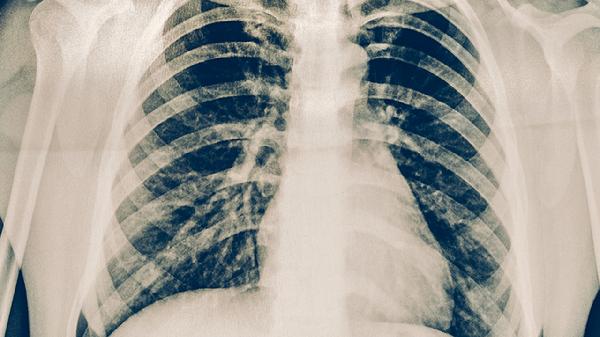

肺結(jié)核患者需避免高糖高脂飲食、辛辣刺激食物、酒精及生冷食物,可適量增加優(yōu)質(zhì)蛋白和維生素攝入。肺結(jié)核是由結(jié)核分枝桿菌引起的慢性傳染病,食療需配合規(guī)范抗結(jié)核治療,避免因飲食不當(dāng)影響藥物吸收或加重癥狀。